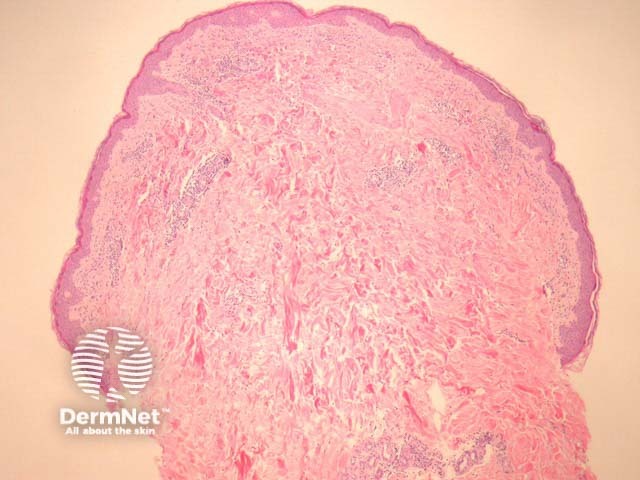

Biopsy of erythema migrans reveals a sparse superficial and deep infiltrate under an uninvolved epidermis (figure 1). Sometimes there is epidermal and/or dermal necrosis. High power examination reveals the infiltrate is mainly lymphocytic (figure 2). There are often sparse eosinophils, admixed plasma cells and mast cells.

Figure 1